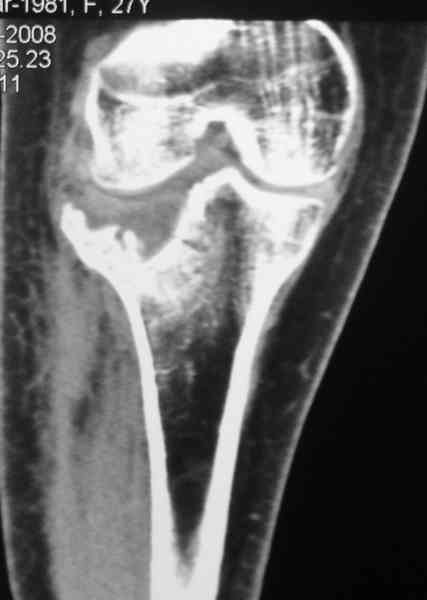

Есть ли возможность сделать КТ?

К большому сожалению КТ пока на ремонте, как запустять, сразу сделаю. Спасибо.

Уважаемый Абдурашид. Если нет противопоказаний , то из оперативных способов, я бы рекомендовал следующие: Полное замещение наружного мыщелка аллотрансплантатом либо открытая репозиция с элевацией и замещение дефекта ауто или аллокостью. В Ваших условиях , я бы рекомендовал второй способ. Во-время элевации необходимо разъединить фрагменты со стороны сустава ( надсечь скальпелем по линиям перелома, а затем тонким остеотомом их разъединить. При помощи долота произвести неполную остеотомию ( захватите не менее 1,5 - 2 см губчатой кости и поднять фрагменты, визуально отрепонировать и фиксировать 2-3 спицами. Дефект заместить костным ауто или аллатрансплантатом. Окончательная стабилизация пластиной ( лучше с угловой стабильностью, либо АВФ - позволит спокойно устранить угловую деформацию.

Недавно поступила больная через 1,5- 2 месяца.

Я согласен с мнением доктора Соломина, что необходимо выполнить СТ. Это поможет Вам не только определить степень повреждения твёрдых тканей, но и увадеть степень сращения. Без СТ не возможно планировать дальнейшую тактику лечения.

У пациента основной проблемой является импрессионый перелом наружного мыщелка, уже неправильно сросшийся, по-видимому. Аппаратом закрыто можно только подправить угол на уровне метадиафиза. Что

улучшит разве что внешний вид конечности, но не решит основной проблемы - грубой деформации суставной поверхности.